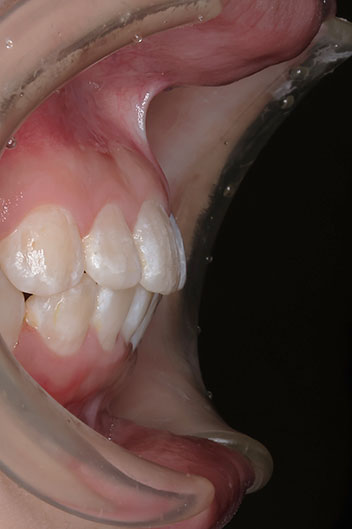

小児矯正での早期治療で、側方拡大による十分なスペース確保をしていたことと、口唇の前突傾向がなかったことから、

平均来院間隔 ほぼ1か月に1度の来院でした。 1か月に1度の来院ですので、治療期間は短く終われました。